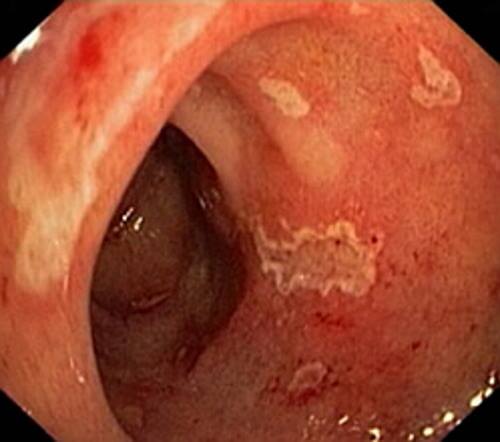

Зображення дуоденоскопа

Найпоширеніший і інформативний метод діагностики бульбита вважається дуоденоскопия. Під час дуоденоскопии вводиться прилад через рот до дванадцятипалої кишки. На кінці дуоденоскопа розташовується маленька камера, яка передає зображення слизової на монітор лікаря, який може виявити вогнища запалення, ерозії, виразки і патології на внутрішній стороні кишечника. Такий метод обстеження є абсолютно нешкідливим і на слизову жодним чином не впливає попадання стороннього тіла в організм. Для того щоб у пацієнта не виникало блювотного позиву, а також до мінімуму знизити дискомфорт, гортань і ротова порожнина попередньо обробляється анестетическим засобом.